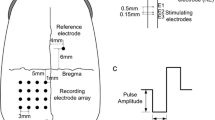

In order to detect the maximal response of EEPs, a nine-recording-electrode array was placed over the visual cortex area (Fig. 1). The skull was exposed through a skin incision at the top of the head along the midline, and nine holes were drilled by a micro bone drill (Micro Motor Handpiece Strong 230, Saeshin Precision Ind. Co., Daegu, Korea) over the visual cortex contralateral to the stimulated eye. The nine holes formed a 3 × 3 array with 2 mm spacing. The center hole was 7 mm anterior to the lambdoid suture and 6 mm lateral to the midline. Nine screw-type stainless steel electrodes (diameter = 800 μm) were screwed into the nine holes respectively to contact the dura mater, and were used for recording the cortical responses. As a reference electrode, a screw-type stainless steel electrode was screwed into the hole which was drilled 6 mm anterior to the bregma suture and 4 mm lateral to the midline contralateral to the recording electrodes. A needle-type stainless steel electrode was placed subcutaneously in the earlobe as the ground electrode.

Schematic diagram of anatomical position for intraorbital optic nerve stimulation and epidural recordings. The right eye was used for electrical stimulation. The stimulating electrode pair with spacing of 1 mm was inserted into the optic nerve intraorbitally, about 1 mm behind the eyeball. The stimulating electrode was anterior to the return electrode, relative to the eyeball. The nine epidural recording electrodes (left, black circles) were placed contralateral to the stimulated eye, forming a 3 × 3 array with 2 mm spacing. The center recording electrode was placed 7 mm anterior to the lambdoid suture and 6 mm lateral to the midline. The epidural reference electrode (right, black circle) was placed 6 mm anterior to the bregma suture and 4 mm lateral to the midline, ipsilateral to the stimulated eye

For electrical stimulation of the optic nerve, the electrodes were inserted into the optic nerve via the intraorbital surgical opening. Each electrode was made of Teflon-insulated tungsten wire with 100 μm core-diameter. The front-end of the stimulating electrode was chemically etched to form a sharp tip with a 300 μm exposure after removal of the insulating layer (Fig. 2). The impedance of the electrode was measured in saline by using a Precision LCR meter (E4980A, Agilent Technologies, Santa Clara, CA, USA) with measured values ranging from 2.5–3.5 kΩ at 1 kHz, 50 mV sinusoidal wave. The stimulating and return electrodes were embedded in an epoxy resin substrate to form an electrode pair. Center-to-center spacing of the electrodes was 1 mm. Under the surgical microscope, the stimulating electrode pair was penetrated through the dura, arachnoid and pia mater and carefully inserted, using ophthalmic forceps, into the optic nerve along its axis. The insertion site of the stimulating and return electrodes was about 1 mm and 2 mm respectively, posterior to the eyeball (Fig. 1).